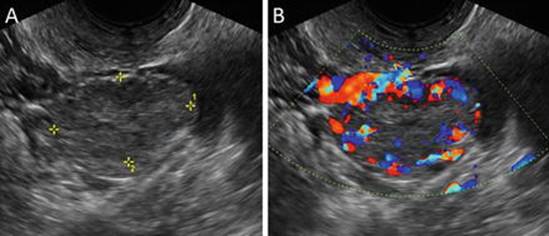

Pelvic ultrasound reveals a small cyst, usually less than 3 cm, with thickened walls, internal echoes, crenulated (collapsing) margins, and peripheral color Doppler flow (Fig. 4.3) [6]. Follow-up for a corpus luteum measuring 3 cm or less is not required, as these most often resolve unless pregnancy occurs, at which point the corpus luteum is “rescued” to secrete progesterone that supports the pregnancy [55]. If the corpus luteum enlarges, hemorrhage into the cyst may occur, resulting in a hemorrhagic cyst (see below).

Fig. 4.3

Corpus luteum. (a) Transvaginal ultrasound reveals a 3-cm corpus luteum (calipers) with internal echoes; (b) peripheral flow is seen by color Doppler